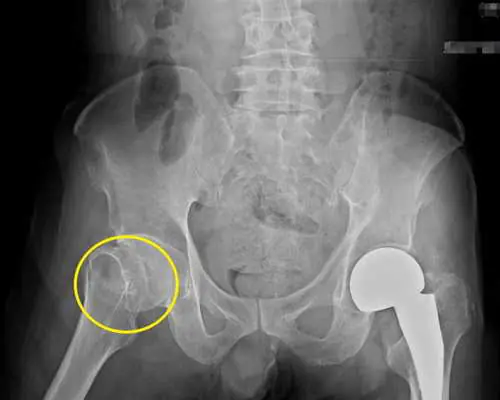

楊醫師檢查發現患者右側髖部出現腫脹,伴隨明顯壓痛,即再安排骨盆X光檢查,發現患者之右側股骨頸骨折,立即安排人工髖關節置換手術,患者術後進行復健治療,已恢復行走能力。

圖一:股骨頸骨折病兆處(圈圈處)。